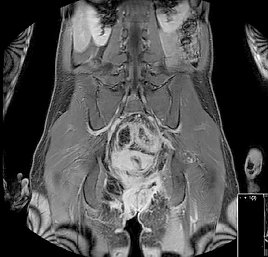

Das MRT wird in der modernen Medizin immer wichtiger, da diese Bildgebung ohne Röntgenstrahlen auskommt und eine sehr gute Option ist, weichteildichte Strukturen mit gutem Kontrast darzustellen. Es muss hier wesentlich unterschieden werden bezüglich der Feldstärke. Während die meisten Systeme heutzutage immer noch 1.5 T basiert sind und niedrigere Feldstärken aufgrund der dann schlechteren Bildqualität immer mehr im Alltag verschwinden, wird in unserer Abteilung zusätzlich das modernste 3 Tesla- MRT-Gerät in Thüringen betrieben. Besonders vorteilhaft ist dieses Gerät in der Beurteilung des Oberbauchs über eine spezielle Technik, die auch die Untersuchungsdauer verkürzt (sog. M-Dixon), aber auch die Beurteilung des Hirns, der Gelenke sowie der Vorsteherdrüse ist qualitativ durch kein anderes Gerät erreichbar. Andere Bildgebungen sind mit 3 Tesla vergleichbar zum ebenfalls auf modernstem Niveau befindlichen 1,5 T System. Im Bereich MRT haben wir in Nord- und Westthüringen in zahlreichen Bereichen besondere Behandlungsschwerpunkte und bieten Untersuchungen an, die sonst weder ambulant noch stationär angeboten werden. Dazu gehört das Prostata-MRT, die Analyse der stofflichen Zusammensetzungen eines Befundes im Kopf über die sog. Spektroskopie, die Darstellung der Nervenbahnen über die sog. Diffusionstensorbildgebung im Hirn, die Erstellung von Ganzkörperaufnahmen in nur 3mm Schichtdicke. Aber auch das Herz-MRT ist durch uns zertifziert hochqualifiziert möglich. Nach aktuellem Stand (5/2013) führt die Radiologieabteilung des Südharzklinikums in Deutschland unter allen Radiologien die achtmeisten registrierten und zertifizierten Herz-MRT durch, nach der Universität Jena die meisten Mamma-MRT in Thüringen. Wir sind europäisches Referenzzentrum für Ganzkörper-MRT und Prostata-MRT und haben über zahlreiche MR-Themen in unterschiedlichen Kongressen publiziert. Die MR-defäkographie kann bei Beckenbodenproblemen sehr hilfreich sein und wird bei uns seit Jahren erfolgreich angewandt. Unser Untersuchungskonzept wurde hier von der Europäischen Röntgengesellschaft als Veröffentlichung für die Ausbildung von Radiologen in ganz Europa angenommen.